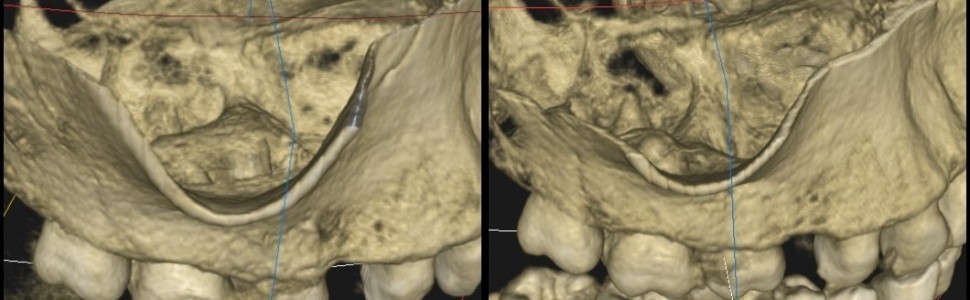

Powtórne leczenie kanałowe należy do rutynowych zabiegów stomatologicznych. Jest to procedura o wiele trudniejsza do przeprowadzenia niż leczenie pierwotne i gorzej rokująca. Dlatego też przed rozpoczęciem leczenia należy przeprowadzić dokładny wywiad, badanie przedmiotowe oraz dodatkowe badania, aby uniknąć błędnego rozpoznania, leczenia i w konsekwencji niepowodzenia leczenia. W niniejszej pracy przedstawiłem opis przypadku zęba gdzie rozpoznaniem wstępnym był ziarniniak zapalny, ostatecznym zaś torbiel korzeniowa. Leczenie obejmowało powtórną endodoncję i leczenie chirurgiczne – resekcję wierzchołków korzeni opisywanego zęba i wyłuszczenie torbieli. W czteroletniej obserwacji klinicznej leczenie takie zagwarantowało sukces terapeutyczny.